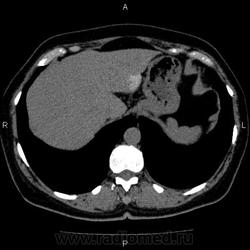

- https://radiomed.ru/sites/default/files/styles/case_slider_image/public/user/5278/10005_1.jpg?itok=0IahzZR6

Это кальцификация. Бывшая гематома, бывший воспалительный процесс, паразитарное поражение, гемангиома, сосудистая мальформация, злокачественное нечто либо метастаз. Без клиники, пола, возраста и болюсного КТ... ну допустим, я поставлю на солитарный метастаз. И это 50/50, т.е. либо я права, либо нет.

гидативную нежизнеспособную кисту. Гемангиома гиподенсна относительно здоровой паренхимы, да и гематома так выглядеть не может.

На эхинококковую кисту похожа

Похоже на кальцинированную эхинококковую кисту печени; для уточнения КТ с болюсным мультифазным контрастированием; консультации гастроэнтеролога и онколога.

"Образование" 3 года без динамики. На УЗИ написали гемангиому. Спасибо всем.